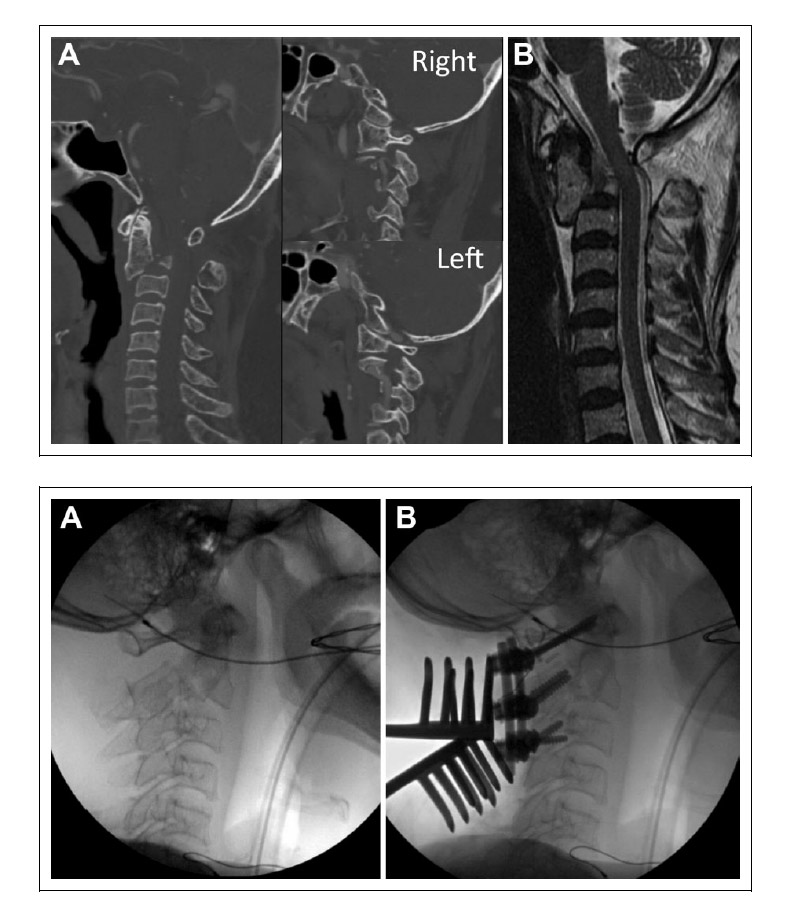

Bello et al 3 presents an example of an MIONM alert in their article on multimodal intraoperative neurophysiological monitoring during positioning of patient prior to cervical spine surgery (shown below).

- Bello JP, Pérez-Lorensu PJ, Roldán-Delgado H, Brage L, Rocha V, Hernández-Hernández V, Dóniz A, García-Marín V. Role of multimodal intraoperative neurophysiological monitoring during positioning of patient prior to cervical spine surgery. Clinical Neurophysiology. 2015 Jun 1;126(6):1264-70.